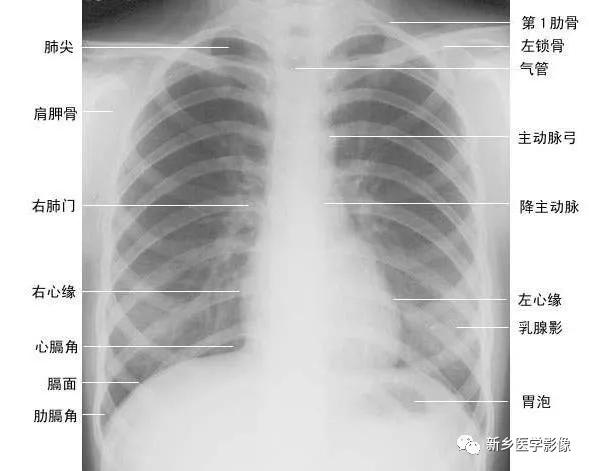

正常胸廓由软组织与骨骼组成,两侧对称(如下图)。

(一)软组织 1、胸锁乳突肌及锁骨上皮肤皱褶 胸锁乳突肌起自胸骨柄及锁骨内端,向后上方斜行,止于乳突,在两肺尖内侧形成外缘锐利且较均匀的致密阴影。在胸骨头和锁骨头及锁骨之间形成一个小三角间隙,叫锁骨上窝或胸锁乳突肌间隙。当颈部偏斜时,两侧胸锁乳乳突肌阴影可不对称,勿误为肺尖部病变。锁骨上皮肤皱褶为与锁骨上缘平行的薄层软组织影,其厚度为3~5mm,内侧与胸锁乳突肌阴影相连,略成直角,系锁骨上皮肤及皮下组织的投影。

2、胸大肌起于锁骨的外侧分,胸骨和第1~6肋软骨,肌束行向外上方,至于肱骨大结节嵴。在肌肉发达的男性,于两肺中部的外侧形成扇形均匀致密影,下缘锐利呈斜行曲线,自肺野伸向腋部,与腋前皮肤皱褶相延续。

3、乳房及乳头 女性乳房于两下肺野形成半圆形的密度增高影,其下缘清楚,并向外与腋部皮肤连续,上缘不清,且密度自下而上逐渐变淡以至消失,其位置随年龄的增长而下垂,一般两侧对称。乳头在两下肺野相当于第5前肋间处形成边缘清楚的小圆形致密阴影,乳房越薄,乳头影境界越清晰,其特点亦为左右对称。青春期乳头呈半球状,约在第2~6肋之间。妊娠期乳腺可明显增大,至哺乳期结束后,乳房逐渐缩小,失去弹性而下垂,到老年期,乳房逐渐萎缩。

(二)骨骼 胸廓前有胸骨、锁骨,后有胸椎、肩胛骨,肋骨则围绕其间。

1、正位肺门影后前位胸片上,肺门位于两肺中野内带第2~4前肋间处,通常左侧肺门比右侧高1~2cm,两肺门的大小和密度大致相等。

(1)右肺门可分为上、下两部。上部约占113,由上肺静脉、上肺动脉及下肺动脉后回归支构成。上肺静脉下后干构成右上肺门的外缘;右肺门下部 约占213,由右下肺动脉干构成,其正常宽度不超过15mm,沿中间段支气管外缘平行向外下走行。右肺门上、下部相交形成一钝的夹角,称肺门角,正常该角顶清晰。

(2)左肺门亦分为上、下两部。上部由左肺动脉及其分支、左上叶支气管和左上肺静脉及其分支构成;下部由左下肺动脉及其分支构成,常被心影所遮盖(如下图)。

在正位胸片上,膈显示为圆顶状阴影,边缘光滑整齐,顶峰靠近中内1/3处。内侧与心脏形成心膈角。外侧与胸壁相交形成肋膈角;在侧位片上,圆顶部靠前,前端与前胸壁形成前肋膈角,后部与后胸壁形成后肋膈角,正常时前、后肋膈角均为锐角,后肋膈角位置最低。右膈顶的位置,一般与第6前肋或第10后肋等高,多数人右膈比左膈高1~2cm,这是因为心脏位置偏于胸腔左侧,故而将左膈压低。膈的位置在正常时可有若干变动:例如儿童膈位置较高,老年人则较低;矮胖型膈位置较高,瘦长型则较低;卧位时膈位置较高,立位时则较低;呼气时膈位置较高,吸气时则较低等。